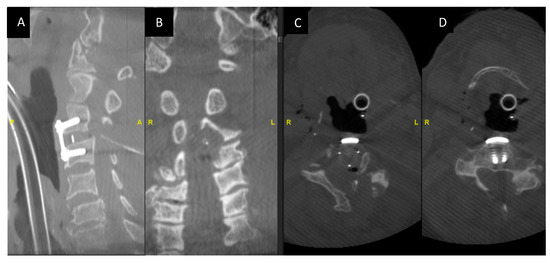

Here, we describe a case of cervical myelopathy with degenerative disc disease and ossified ligamentum flavum at the c3 level (Figure 1A–D).

Figure 1.

(A,B): MRI showing severe central canal and severe bilateral neural foraminal stenosis at C3-4 with compression on the spinal cord and focal gliosis/myelomalacia/ Figure 2 (C,D) show CT images of C34 OLF, C34 and C56 listhesis.